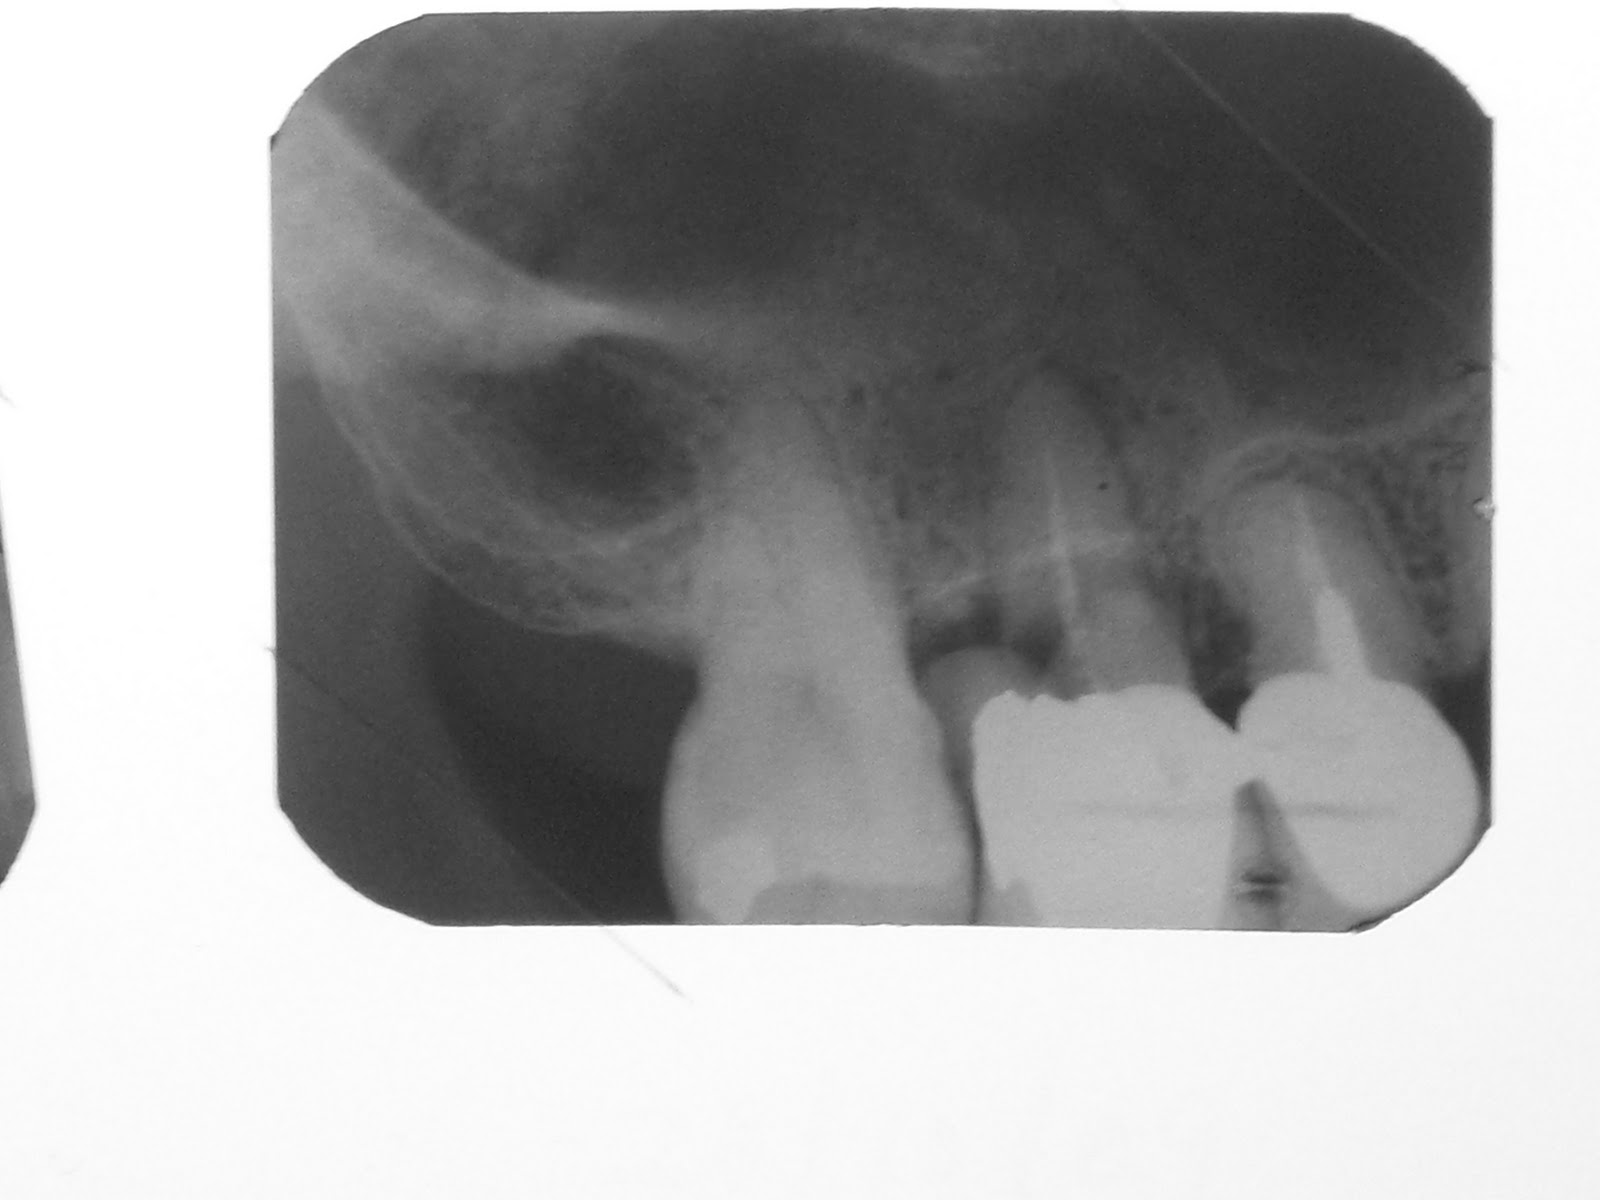

Now, what do we do? We put in two implants for the laterals of course! What sort of dental implants? Ahhhhhhh......... Conventionals are out of the question. Minimized dental implants of course! Even then, we still had to graft the labial surfaces of the laterals to increase the thickness because there was only a wafer thin layer of bone there...... having had no teeth there before at all.... congenitally missing. Here then is a classic case of minis being the treatment of choice!

After grafting the lateral labial surfaces, we place in the minis.